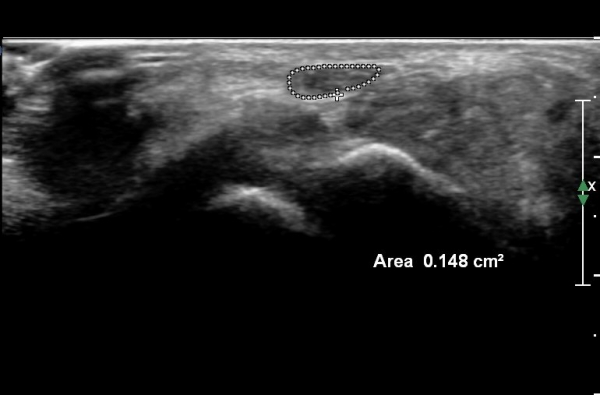

¼Õ¸ñ ºÎÀ§¿¡¼­ Á¤Á߽Űæ Ⱦ´Ü¸é°Ë»ç»ó Á¤Á߽ŰÜÀÇ Àú¿¡ÄÚ ºÎÁ¾ÀÌ °üÂûµÊ(»çÁø 1).

¼ö±Ù°ü ±ÙÀ§ºÎ(scaphoid, lunate level)¿¡¼­ Á¤Á߽Űæ Ⱦ´Ü¸é°Ë»ç»ó Á¤Á߽ŰæÀÇ Àú¿¡ÄÚ ºÎÁ¾ÀÌ °üÂûµÊ.(»çÁø 2).

¼ö±Ù°ü ¸»´ÜºÎÀ§(trapezium, capitate level)¿¡¼­ Á¤Á߽Űæ Ⱦ´Ü¸é°Ë»ç»ó Á¤Á߽ŰßÀÇ ÆíÆòÈ­°¡ °üÂûµÊ(»çÁø 3).

Á¤Á߽Űæ Á¾´Ü¸é°Ë»ç»ó ¼ö±Ù°ü ¸»´Ü(trapezium, capitate level)  µÎ²¨¿öÁø È¾¼ö±ÙÀδë(transverse carpal ligament)¿¡

ÀÇÇÑ Á¤Á߽ŰæÀÇ ±¹¼ÒÀû ¾Ð¹ÚÀÌ °üÂûµÊ(»çÁø 4, 5).